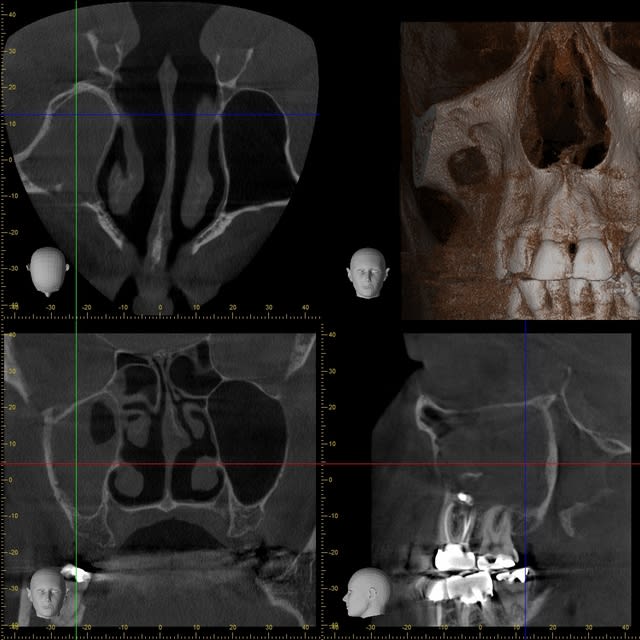

Que pensez-vous de cette bouse très radio-opaque dans le sinus maxillaire gauche ?

Pâte à canaux (un pot entier) ?

Noyau de pêche ?

Boulette de shit ?

Comblement de sinus au MTA par voie endocanalaire !

Vu la quantité, on comprends qu'il a les moyens ton patient !